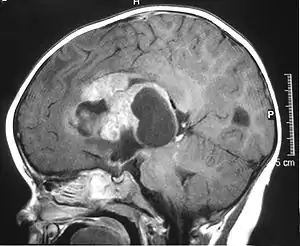

The initial diagnosis of a tumor is made with a radiographic study (MRI[20] or CT-). If CT was performed first, an MRI is usually performed as the images are often more detailed and may reveal previously undetected metastatic tumors in other locations of the brain. In addition, an MRI of the spine is usually performed. The AT/RT tumor often spreads to the spine. AT/RT is difficult to diagnose only from radiographic study; usually, a pathologist must perform a cytological or genetic analysis.

Appearance on radiologic exam

AT/RTs can occur at any sites within the CNS; however, about 60% are located in the posterior fossa or cerebellar area. The ASCO study showed 52% posterior fossa; 39% sPNET; 5% pineal; 2% spinal, and 2% multifocal.[1]

The tumors' appearance on CT and MRI are not specific, tending towards large size, calcifications, necrosis (tissue death), and hemorrhage (bleeding). Radiological studies alone cannot identify AT/RT; a pathologist almost always has to evaluate a brain tissue sample.

The increased cellularity of the tumor may make the appearance on an uncontrasted CT to have increased attenuation. Solid parts of the tumor often enhance with contrast MRI finding on T1 and T2 weighted images are variable. Precontrast T2 weighted images may show an isosignal or slightly hypersignal. Solid components of the tumor may enhance with contrast, but not always. MRI studies appear to be more able to pick up metastatic foci in other intracranial locations, as well as intraspinal locations.

Preoperative and follow-up studies are needed to detect metastatic disease.